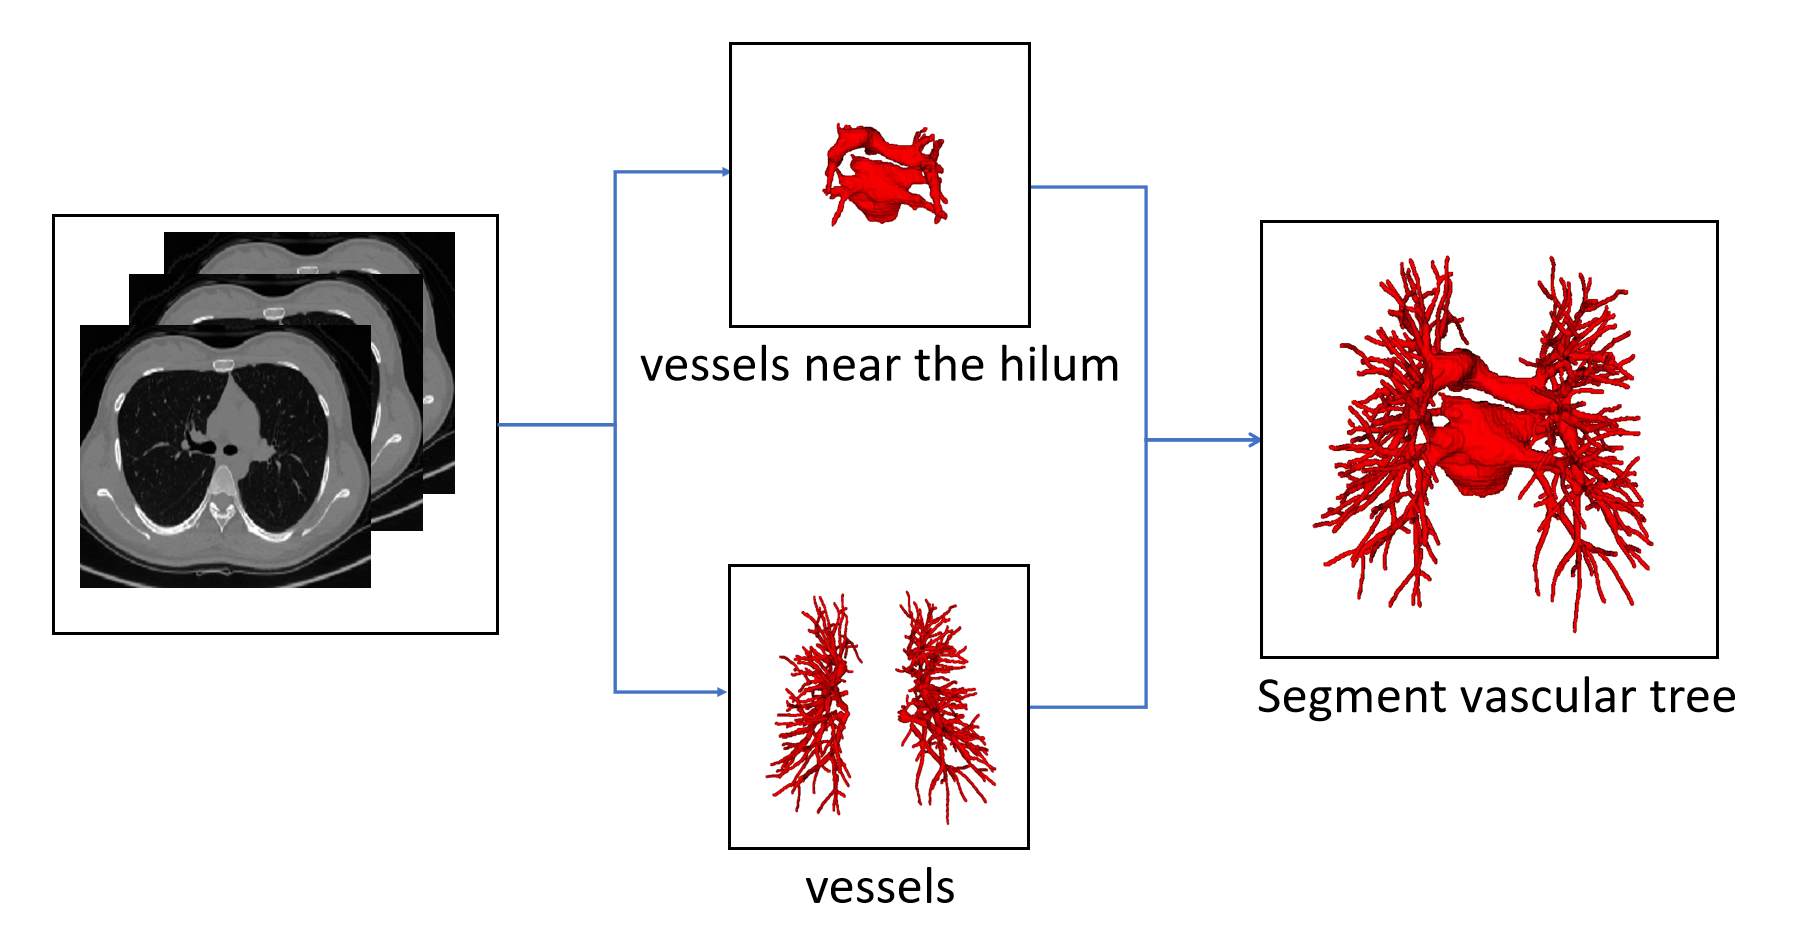

The proposed method begin with vascular tree segmentation. Vascular trees are extracted from chest CT scan by fusion of vessels[15] and vessels near the hilum of the lung. The specific process is shown in Fig. 4. And then, topology tree is constructed by skeleton topology extraction.

In order to reconstruct pulmonary A/V, base on the refined prediction and scale of center voxels, each voxel in the scale region is labeled with the corresponding prediction of center voxels. It is then fused with vessels near the hilum of the lung for final A/V results.

Our evaluation method for A/V separation is based on topological particles rather than voxel classification. This finding is mainly due to the difficulty of obtaining accurate annotations of pulmonary vessels based on voxel levels, which are also indistinguishable by doctors. In addition, in clinical practice, doctors focus more on the structural branching direction of vessels, consistent with the evaluation system based on topological particles. A/V separation can provide effective information for doctors to make surgical plans and perform surgical navigation, and proximal vascular extension can help doctors to locate the vessel more quickly. Therefore, the final A/V separation results include vessels close to the hilum of the lung, as shown in Fig. 12. Our evaluation system for the method of A/V separation do not include vessels near the hilum of the lung mainly because the vessels near the hilum are abnormally large and nontubular, and the vascular topology could not be extracted.